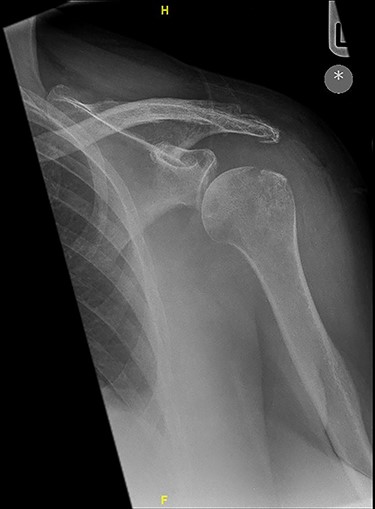

Six months post-surgery—profound loss of joint space and superior subluxation.

X-ray images 6 months later showed the devastating effect of the infection with a profound loss of joint space and superior subluxation in keeping with loss of rotator cuff muscles.